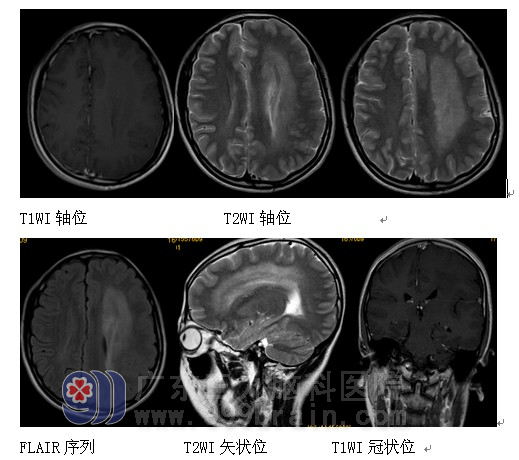

MRI检查:左侧大脑半球弥漫性肥大,左侧侧脑室前后角旁及左侧半卵圆中心示多发片状稍长T1长T2异常信号影,FLAIR序列呈高信号,增强后病变未见强化,左侧侧脑室前角受压、轻度变窄,双侧侧脑室后角轻度扩大,左侧大脑半球脑回肥厚,局部脑沟减少、变浅。胼胝体短小。MRS检查:感兴趣区为左侧侧脑室前角旁病变,谱线显示NAA峰略有下降,Cho峰未见升高,Cho/NAA比值0.73。诊断:左侧巨脑畸形伴胼胝体发育不良。